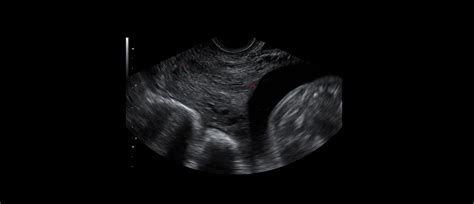

- Med 20. in 24. tednom nosečnosti: V tem obdobju se pogosto priporoča ultrazvočno merjenje dolžine materničnega vratu, saj lahko že takrat zaznamo morebitne spremembe, ki bi lahko nakazovale na povečano tveganje za prezgodnji porod.

- Normalna dolžina: V zgodnejših tednih nosečnosti (npr. 13. teden) je dolžina 3 cm lahko povsem normalna. Med 20. in 24. tednom je dolžina materničnega vratu, ki je manjša od 20 mm, povezana s povišanim tveganjem za prezgodnji porod. Dolžina 30 mm ali več v tem obdobju običajno še ne predstavlja resne skrbi.

- Ultrazvočno merjenje: Če dvomite o natančnosti ocene ali želite dodatno potrditev, se lahko odločite za samoplačniški ultrazvočni pregled.

- Tekočina v fornikusu: V enem izmed primerov je omenjena tekočina v zadnjem fornikusu. Čeprav natančen pomen tekočine ni vedno jasen in jo je težko interpretirati brez slike, v nekaterih primerih lahko gre za cervikalno sluz, ki se na UZ prikaže kot tekočina. Če je maternični vrat zaprt in test na plodovnico negativen, te skrbi pogosto niso upravičene.